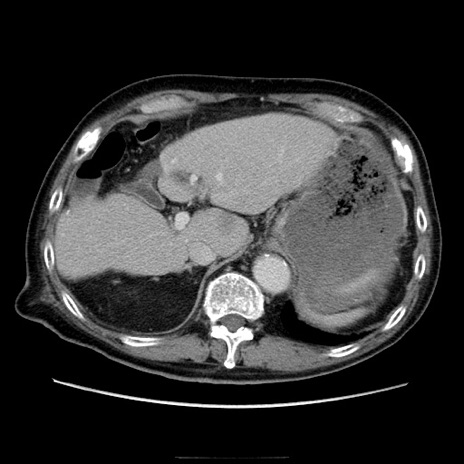

症例21(横断像)

【症例】70歳代男性

【主訴】腹痛

【現病歴】肝硬変・肝細胞癌にてかかりつけの方。約9時間前に食後より腹痛出現。症状が徐々に増悪し、嘔吐出現したため来院。

【既往歴】肝硬変、肝細胞癌(RFA、TACE後)

【身体所見】意識清明、表情苦悶様、BT 36℃、BP 129/78mmHg、P 88bpm、SpO2 97%(RA)、右上腹部から心窩部にかけて圧痛あり、反跳痛なし、筋性防御あり。

【データ】WBC 5800、CRP 0.16